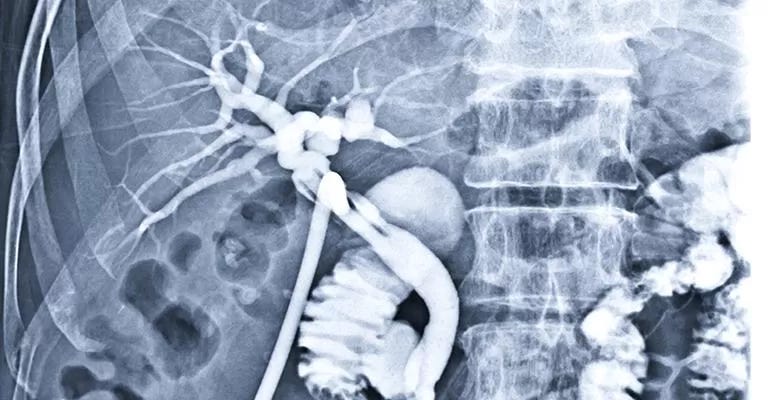

Cirrhosis of the liver and the subsequent elevation of portal pressure is more prevalent in areas where hepatitis is common and also where alcohol abuse is present. The development of oesophageal varices frequently leads to recurrent episodes of bleeding, which can be quite severe and life threatening. Surgical measures to reduce the portal pressure such as porto-caval shunts have long been practiced however the bulk of management is now based on the use of beta blockers, local treatment of bleeding by endoscopists and the formation of intrahepatic shunts under image guidance. Transjugular intra hepatic porto-systemic shunt (TIPS) is now the treatment of choice for uncontrollable variceal bleeding and other manifestations of portal hypertension and liver disease such as persistent ascites. This procedure is performed, as its name indicates, by advancing a catheter from the right jugular vein into the hepatic vein and then creating a track through the liver into the portal vein followed by dilatation of the track and the insertion of a covered stent across the track that connects the systemic circulation with the portal circulation (Fig 2). The size of the stent is chosen according to the clinical situation and the level of portal pressure. Generally, a gradient of less than 12mmHg is required across the shunt to achieve a satisfactory outcome. There are other medical measures to reduce the incidence of encephalopathy that can happen after any form of porto-systemic shunt creation. The varices may be embolised through the shunt that provides access to the portal system and its tributaries. One of the main advantages of TIPS in addition to the minimally invasive non-surgical approach, is that it does not prevent future liver transplantation.